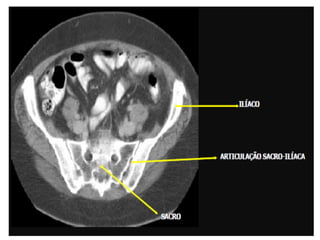

Varredura da Pelve

• Os limites são definidos pela extremidade

superior da crista ilíaca até a extremidade

inferior do ísquio.

• Os pacientes devem ser posicionados em

decúbito dorsal sem angulação do gantry.